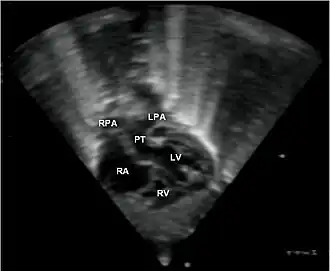

- Les coupes échographiques les plus utiles à cette fin sont :

- La coupe parasternale gauche grand axe : elle montre que le vaisseau issu du ventricule gauche (le plus postérieur) se dirige anormalement vers l'arrière et se bifurque précocement. C'est donc le tronc pulmonaire et non l'aorte comme normalement.

- Les coupes sous costales qui montrent bien le trajet parallèle des gros vaisseaux et leur inversion. Cet examen permettra d'éliminer en particulier un retour veineux pulmonaire anormal total bloqué qui aurait pu rendre compte de l’hypervascularisation pulmonaire sur la radiographie des poumons.